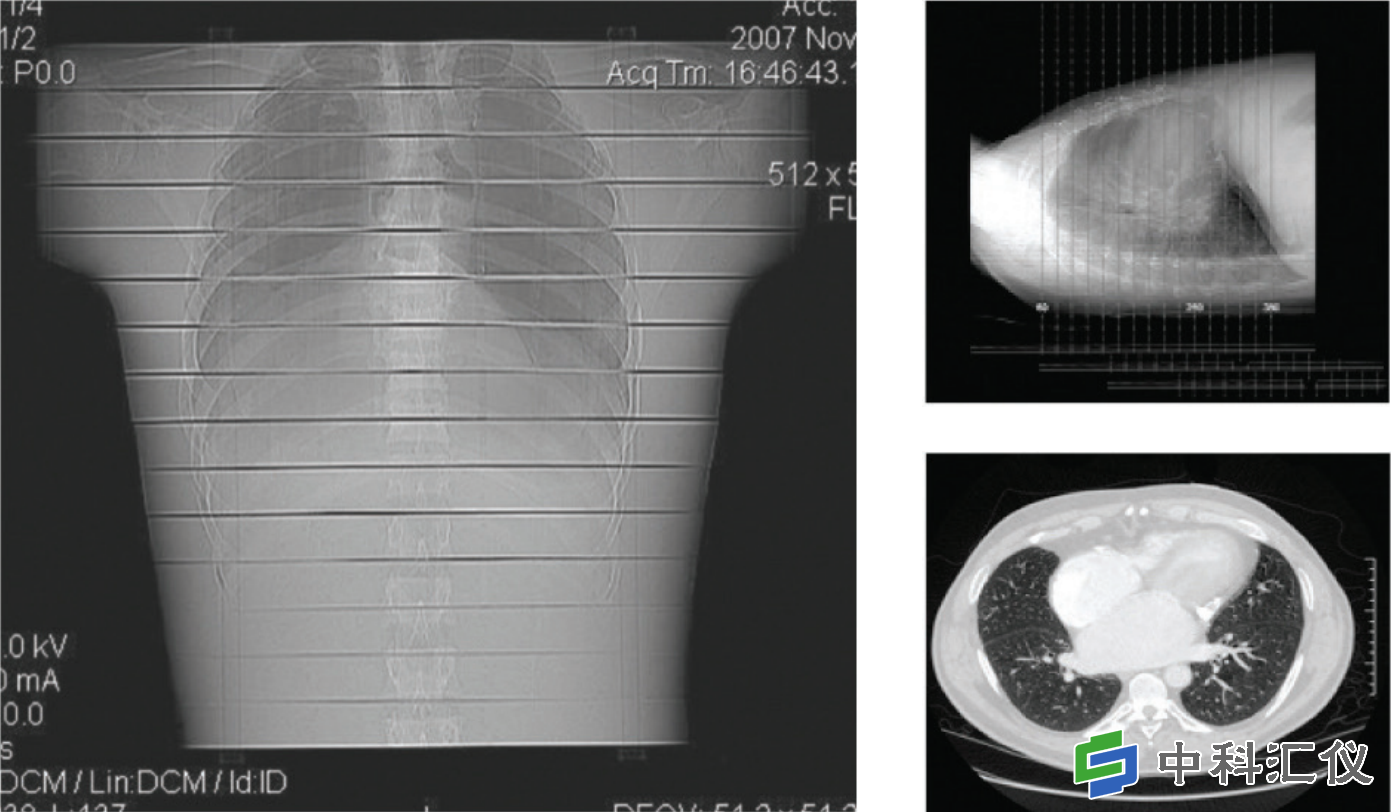

胸部模型剂量测定应用

典型的胸部辐射分析。结果取自一项体内研究,该研究使用 CT 扫描仪对胸部进行 64 层切片检查。

实际结果显示了典型模型曝光下 Gafchromic™ LD-V1 胶片的一条条带。